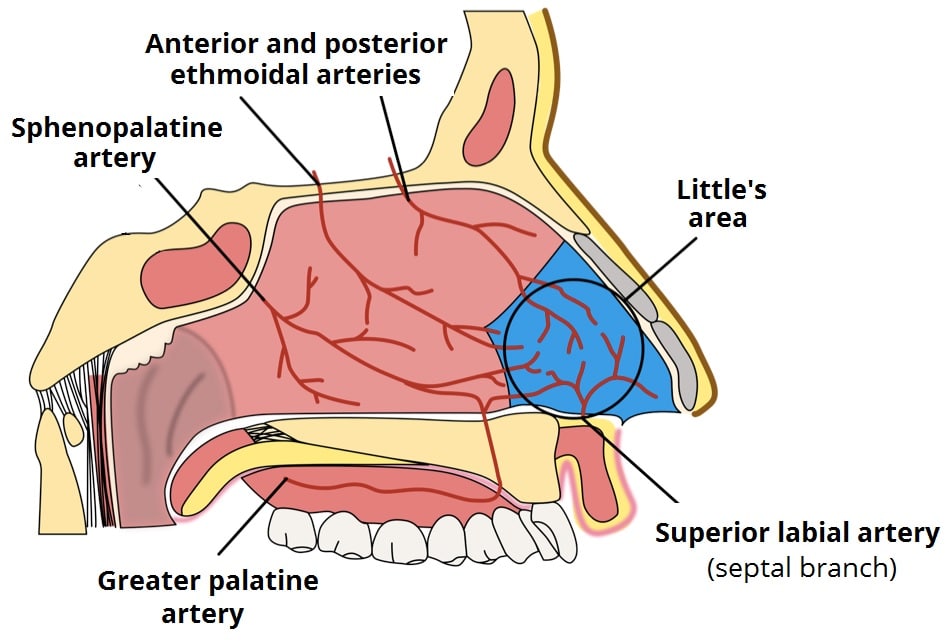

The Nasal Cavity Structure Vasculature Innervation

The Nasal Cavity Structure Vasculature Innervation

The Nasal Cavity Structure Vasculature Innervation

The Nasal Cavity Structure Vasculature Innervation